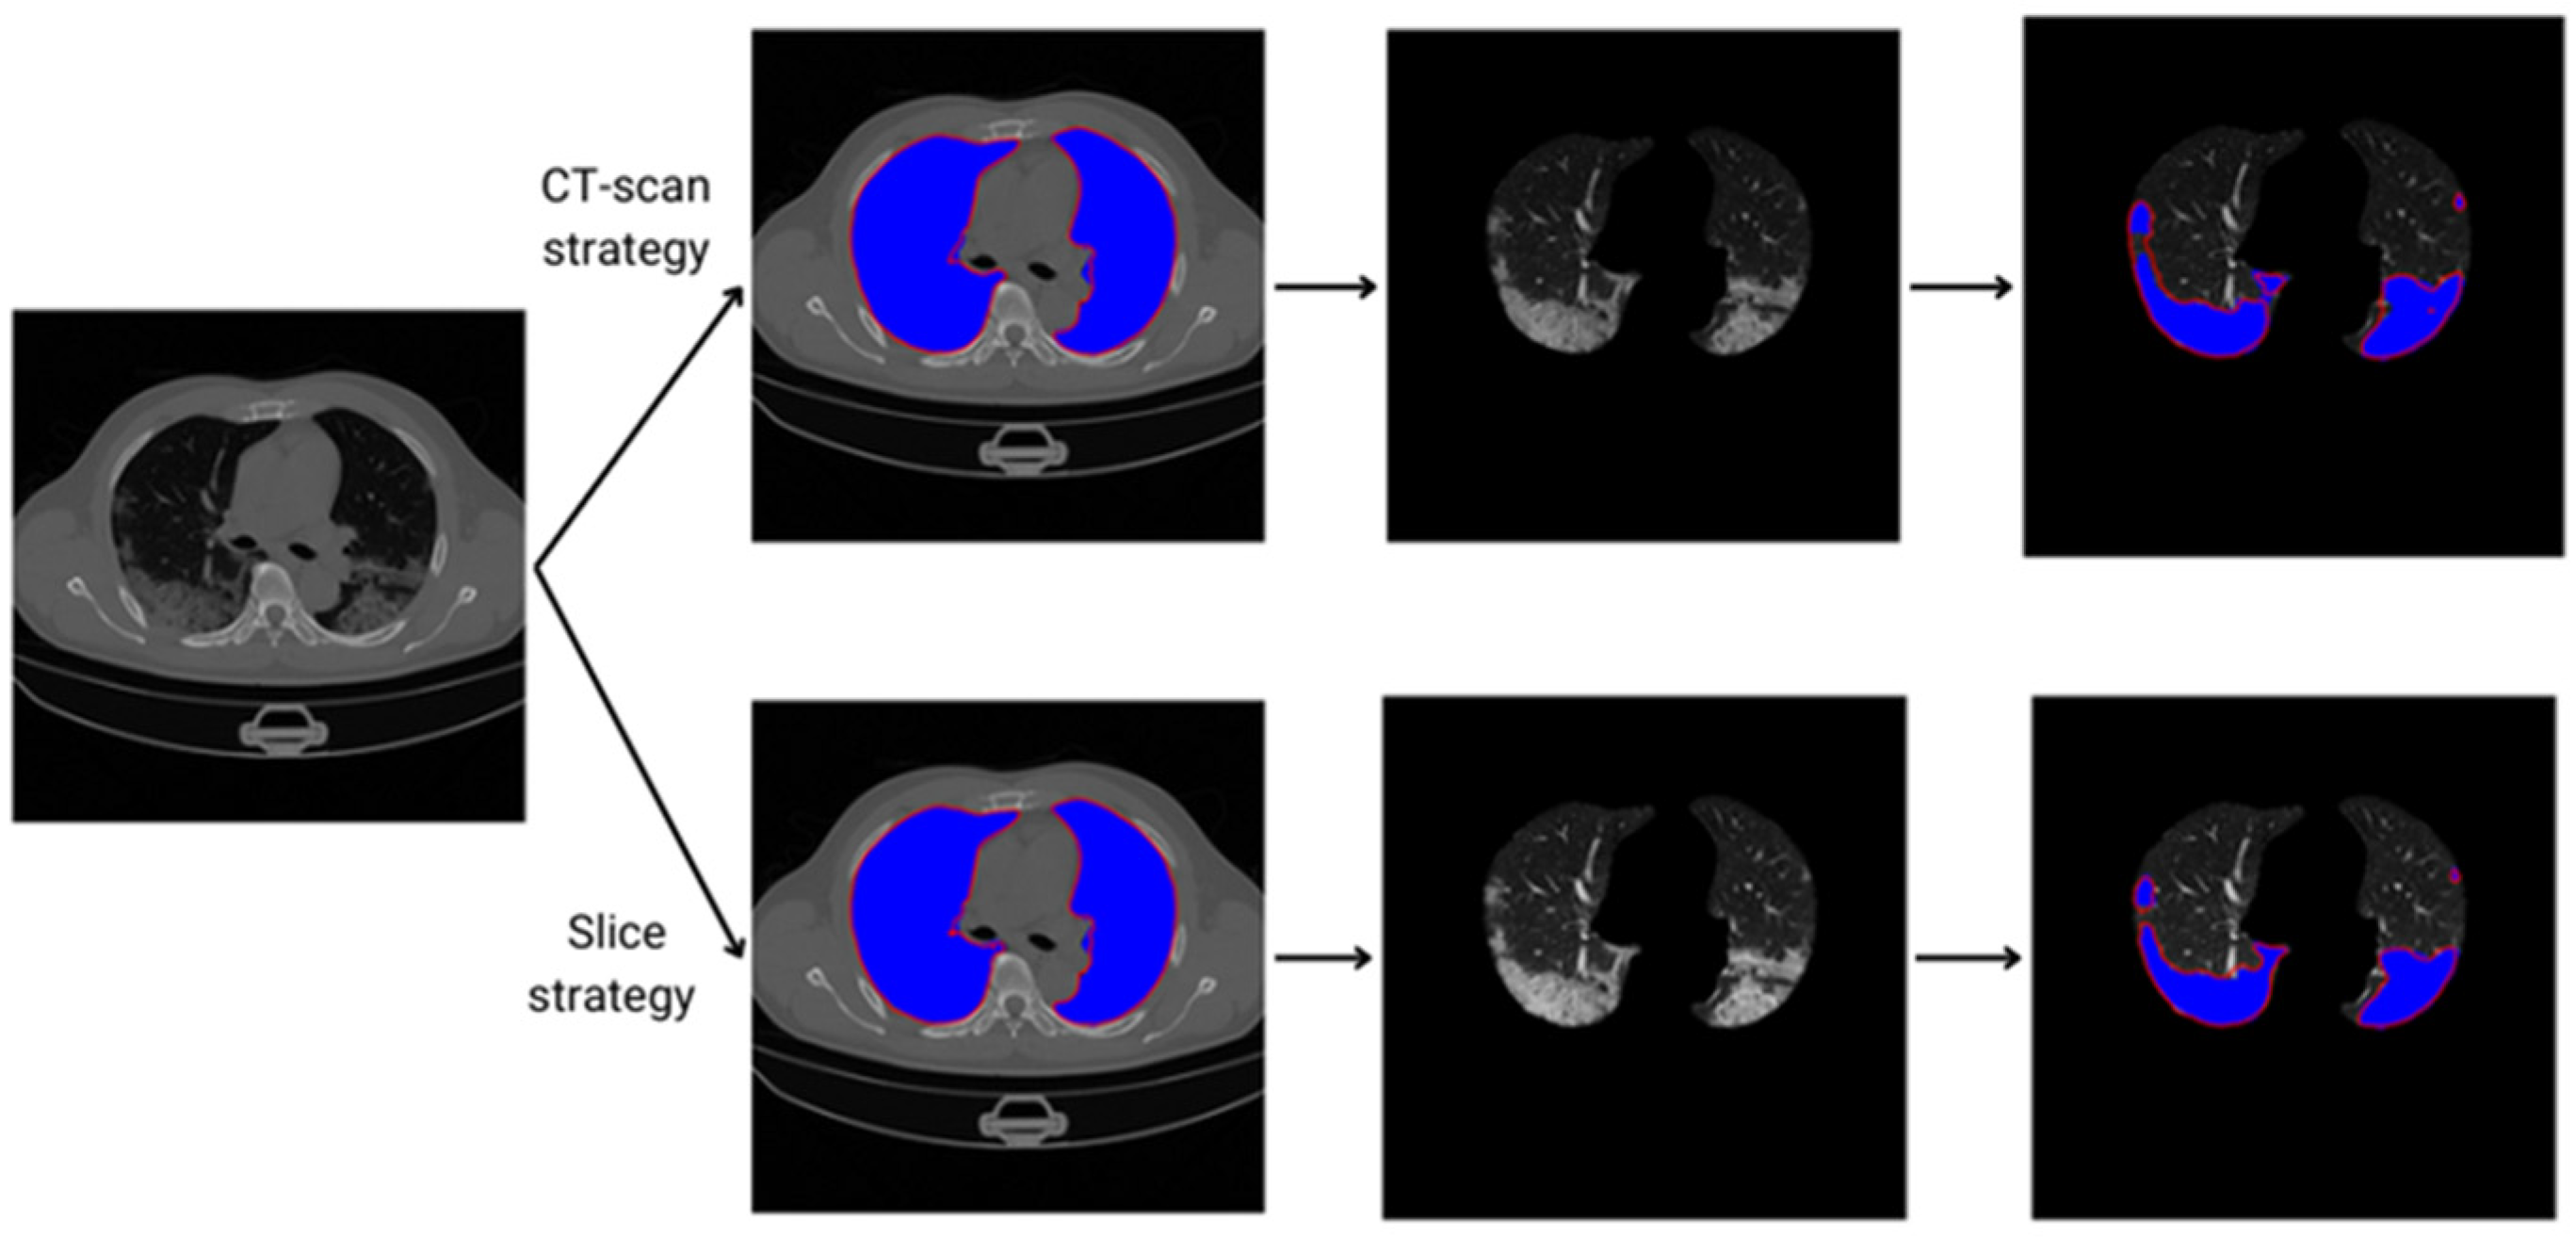

- Using CT images, we compare the performance of deep learning tools by employing the two-step segmentation method for COVID-19; we use both the data partitioning strategies, i.e., CT-scan and slice methods.

2.2.2. DP Strategies for Training, Validation and Testing

2.2.4. Lung and COVID-19 Segmentation